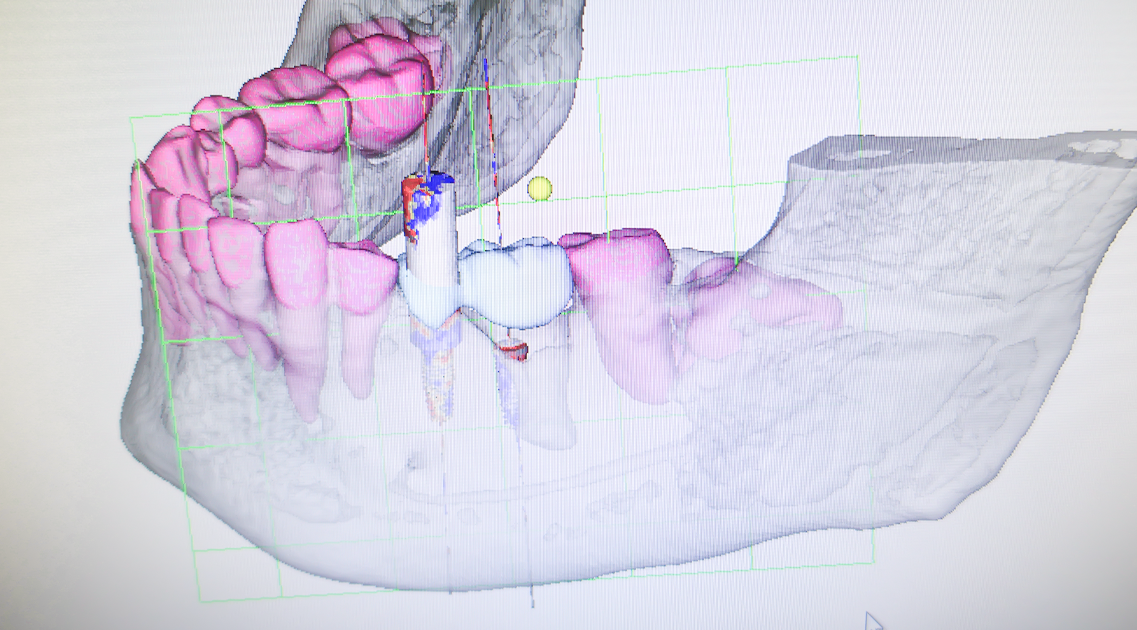

BioNaシミュレーション画像

歯牙支持型フラップレス